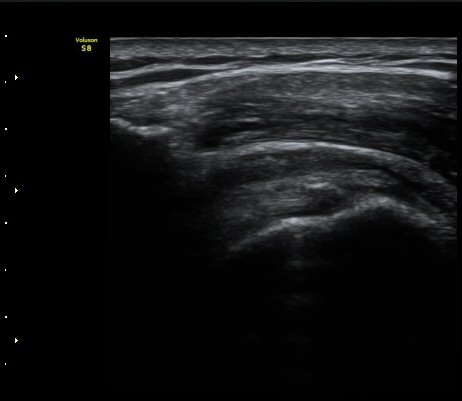

±Ø»ó°Ç Á¾´Ü¸é°Ë»ç¿¡¼­ Á¤¸Æ³¶³» ¼ö¾×Àú·ù¿Í ±Ø»ó°Ç³» ¼®È¸È­À½¿µÀÌ °üÂûµÈ´Ù(±×¸² 2, 3).